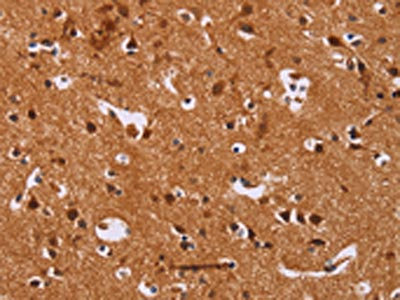

The image on the left is immunohistochemistry of paraffin-embedded Human brain tissue using CSB-PA182905(CALCA Antibody) at dilution 1/25, on the right is treated with synthetic peptide. (Original magnification: ×200)